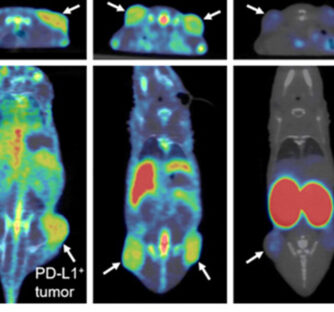

Optimizing immunoPET imaging of tumor PD-L1 expression